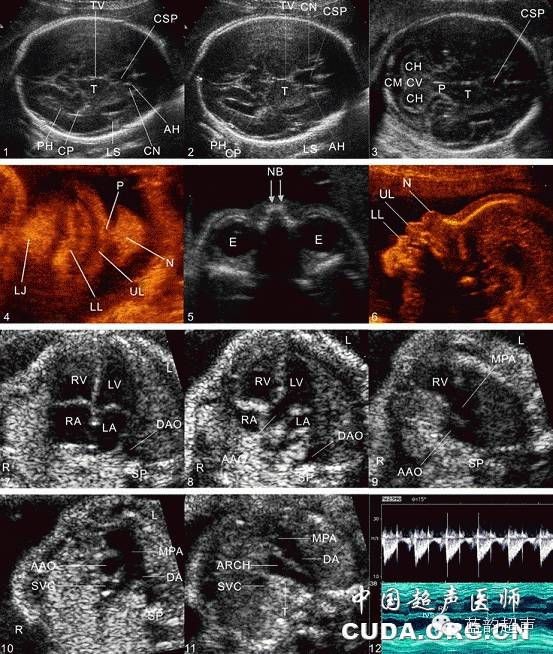

Ⅱ级产科超声检查建议存留的超声图与模式图

1、丘脑水平横切面超声图与模式图,2、小脑水平横切面超声图与模式图,3、四腔心切面超声图与模式图,4、上腹部横切面超声图与模式图,5、脐带腹壁插入口横切面超声图与模式图,6、膀胱水平横切面超声图与模式图,7、双肾横切面超声图与模式图,8、左肾及右肾矢状切面超声图与模式图,9、双肾冠状切面超声图与模式图,10、脊柱矢状切面超声图与模式图,11、股骨长轴切面超声图与模式图,12、孕妇宫颈内口矢状切面超声图与模式图,13、测量胎心率图(多普勒或M型)超声图及模式图,14、胎盘厚度测量超声图及模式图,15、最大羊水池切面超声图及模式图TV:第三脑室,T:丘脑,CSP:透明隔腔,PH:侧脑室后角,CP:脉络丛,LS:大脑外侧裂,CN:尾状核,AH:侧脑室前角,P:大脑脚,CH:小脑半球,CV:小脑蚓部,RV:右心室,LV:左心室,LA:左心房,RA:右心房,DAO:降主动脉,UV:脐静脉,IVC:下腔静脉,AO:腹主动脉,ST:胃泡,UAS:脐动脉,BL:膀胱,RK:右肾,LK:左肾,VA:椎弓,VB:椎体,FL:股骨,CX:宫颈,BL:膀胱